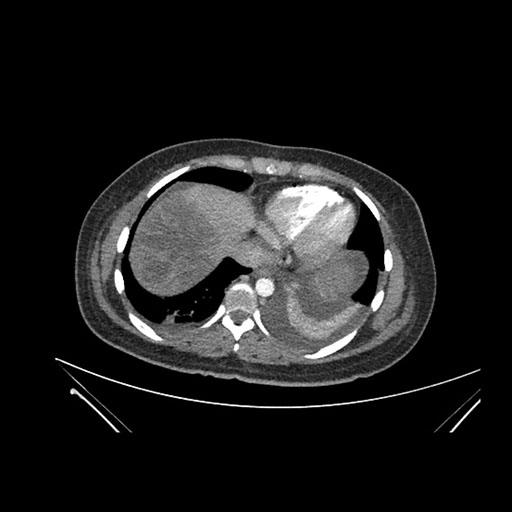

Axial Arterial

Axial Venous

Imaging analysis

Based on initial findings, which issue(s) would you be most concerned about?